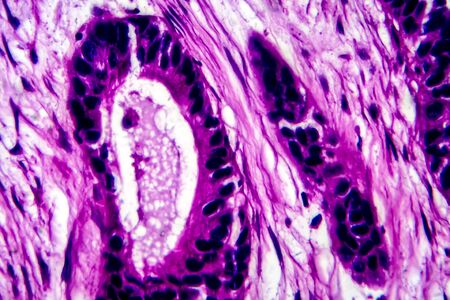

High magnification of a human prostatic gland. A simple columnar epithelium surrounds a very irregular lumen. Hematoxylin & eosin stain.

Photomicrograph showing histological features of benign prostatic hyperplasia. Enlarged prostate gland with nodular proliferation of glandular and stromal components.

Photomicrograph showing histological features of benign prostatic hyperplasia. Enlarged prostate gland with nodular proliferation of glandular and stromal components.

Low magnification of a human prostate gland in a 70-year-old man. The prostate gland appears with dilated alveoli, which contains many corpora amylacea (prostatic concretions) in their lumen. Light microscope micrograph. Hematoxylin & eosin stain.

Human seminal vesicle. The surface of the mucosa is very folded. The spaces that look like glands are really infoldings of the mucosa that communicate with the lumen. The epithelium is pseudostratified columnar with basal cells.